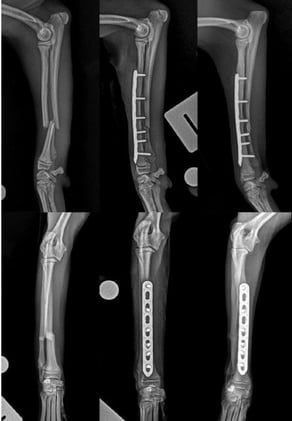

MusculoskeletalMusculoskeletal